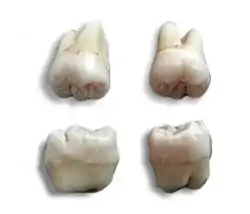

Morphology of wisdom teeth can be variable.

Maxillary (upper) third molars commonly have a triangular crown with a deep central fossa from which multiple irregular fissures originate. Their roots are commonly fused together and can be irregular in shape.

Mandibular (lower) third molars are the smallest molar teeth in the permanent dentition. The crown usually takes on a rounded rectangular shape that features four or five cusps with an irregular fissure pattern. Roots are greatly reduced in size and can be fused together.[13]